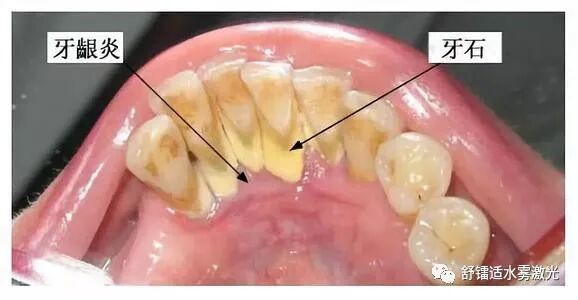

龈上牙结石,也叫可见牙结石,一般是覆盖在牙缝,牙背,牙根部,肉眼能看到;

龈下牙结石,也叫不可见牙结石,这种牙结石已经侵入到了牙龈下了,一般伴随有牙龈出血,肉眼不能看到。

牙龈下面的牙结石肉眼看不到,一般呈褐色或者黑色,附着更坚固,而且牙结石易吸附细菌/毒素,再加上本身对牙周组织的刺激,会使牙龈内侧溃疡,不易愈合,导致牙龈出血,牙周疾病加重,口臭,牙周袋,牙齿松动甚至脱落等。

其实这就是龈下牙石,附着在我们牙根表面,位于牙龈下方的牙结石。对于这些牙结石,普通的洗牙就显得束手无策了,需要医生为患者进行龈下刮治术。